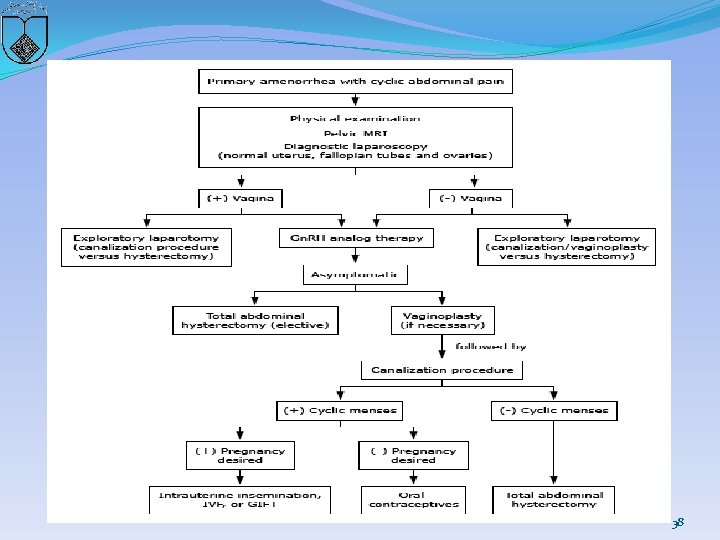

�A treatment algorithm �clinicians should select a surgical procedure carefully and be certain of the diagnosis (eg, differentiate between a high transverse vaginal septum and cervical agenesis) �A safe, successful surgical procedure is more likely when there is normal cervical tissue that just lacks a patent cervical canal than when there is significant cervical agenesis. 35

36

37

38

�Advances in reproductive endocrinology and fertility therapy have enabled women to avoid the need for surgical intervention. � Long-term use of medications that suppress menstruation (eg, combination estrogen/progestin therapy, continuous progestin only, or a Gn. RH agonist with add-back therapy) can prevent development of hematometra, dysmenorrhea, and chronic pelvic pain. � When pregnancy is desired, these medications can be stopped and conception may be attempted using assisted reproductive techniques. �Successful pregnancies with planned cesarean delivery have been reported 39